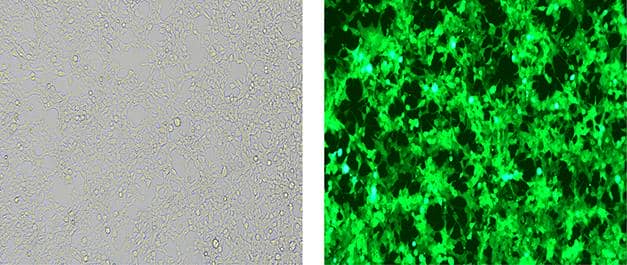

三、細(xì)胞轉(zhuǎn)染

細(xì)胞轉(zhuǎn)染是將外源的DNA,RNA等分子導(dǎo)入到真核細(xì)胞,普健生物可提供質(zhì)粒,siRNA,mimic,inhibitor等轉(zhuǎn)染到宿主細(xì)胞中。

案例展示

細(xì)胞培養(yǎng)及轉(zhuǎn)染服務(wù)